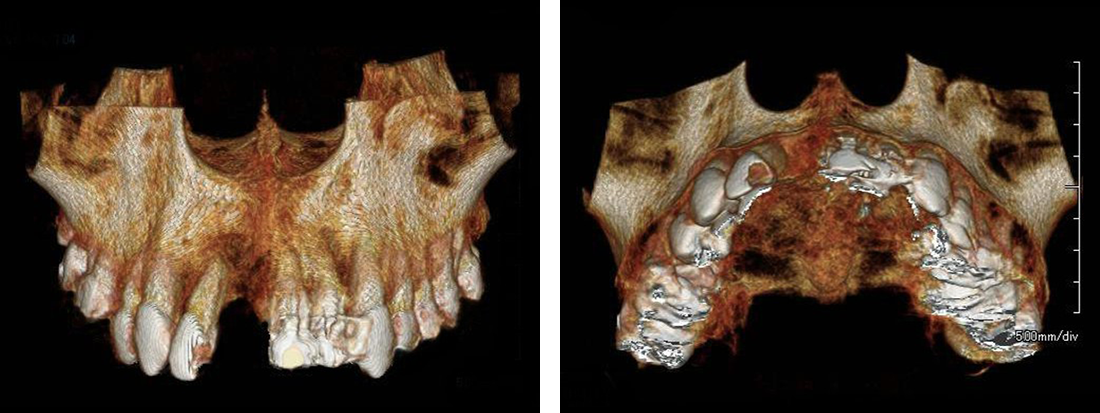

CT事前にシュミレーション

シュミレーション通りにインプラント埋入

局部麻酔のもと、顎の骨にチタン製のインプラントを挿入します。 このインプラントが 新しい歯の土台となります。